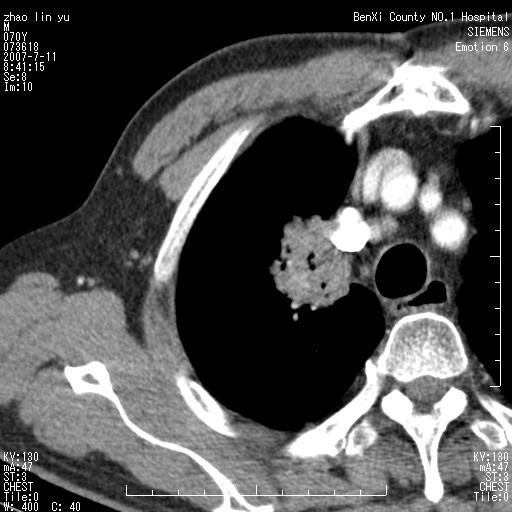

以下是引用王靖旗在2007-7-10 17:12:00的发言:[br] 男、70、咳嗽两个月,半年前换瓣手术,胸片未见异常,于昨天行x片发现右肺上野大片影,行ct扫描,这里是减薄图像,余肺正常。明天晚上会有增强扫描片,到时我会上传。[br][br] 冠状位请大家细看,应该是有意义的,[br][br] 请大家先看平扫发表意见。[br][br]

以下是引用zhangzhongshou在2007-7-10 21:43:00的发言:[br]右肺上叶周围型肺癌,以孤立型细支气管肺泡癌可能性大。